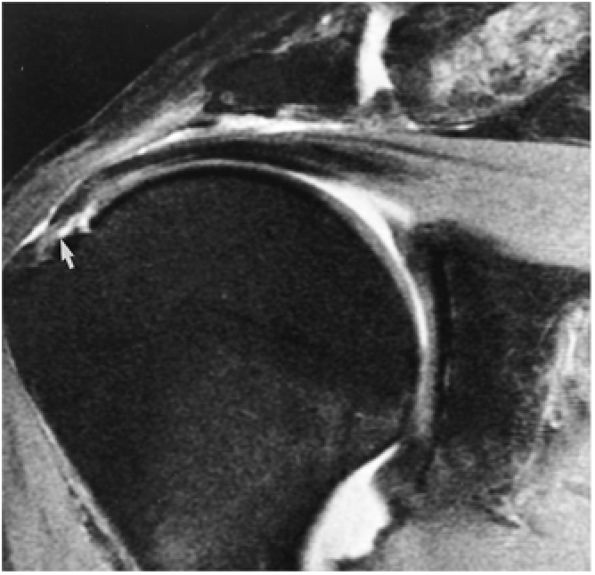

tendon tears and may result from fluid entering the muscle via a one-way valve mechanism through a partial-thickness tendon tear.